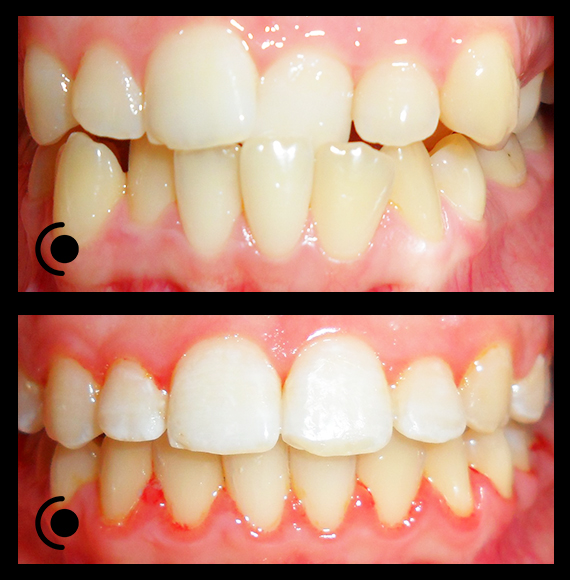

O našoj kvaliteti najbolje govore naši rezultati!

Centar za ortodonciju Petra Džapo